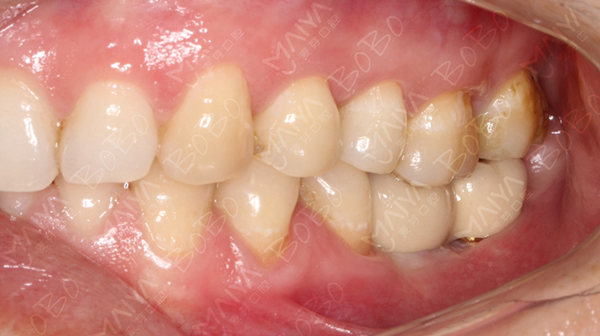

种植完成后的牙齿情况